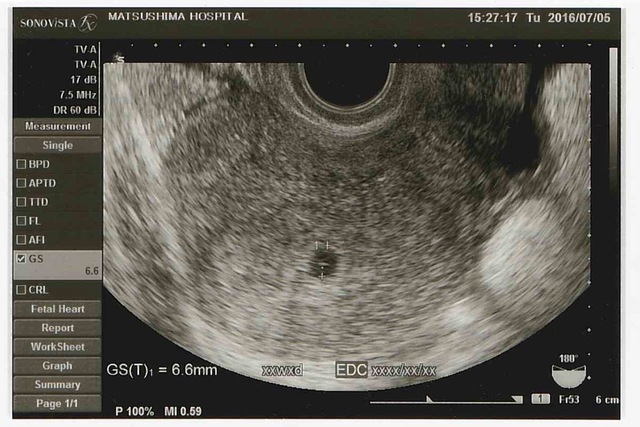

4週0日(4w0d・女の子)|hahyhah さん(27歳)

エコー写真撮影時のエピソード:

はじめてのエコー写真。

まだ心拍も確認出来ていないけど、胎嚢が確認出来た。 しっかりと妊娠が確認出来て一安心。